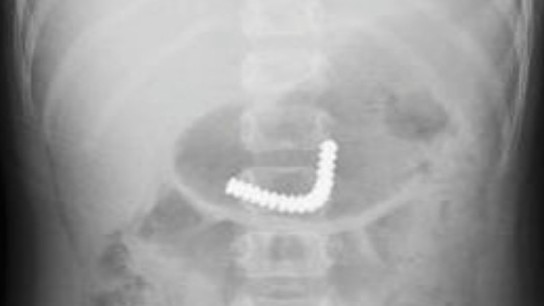

18 viên nam châm kết chùm trong ruột bé trai

Hướng dẫn nuôi dạy con -  23/12/2020

Sáu giờ trước khi vào Bệnh viện Nhi đồng Thành phố hôm 21/12, bé cầm chơi rồi nuốt các nút nam châm này. Sau đó bé không đau bụng, không ói nhưng vô c...